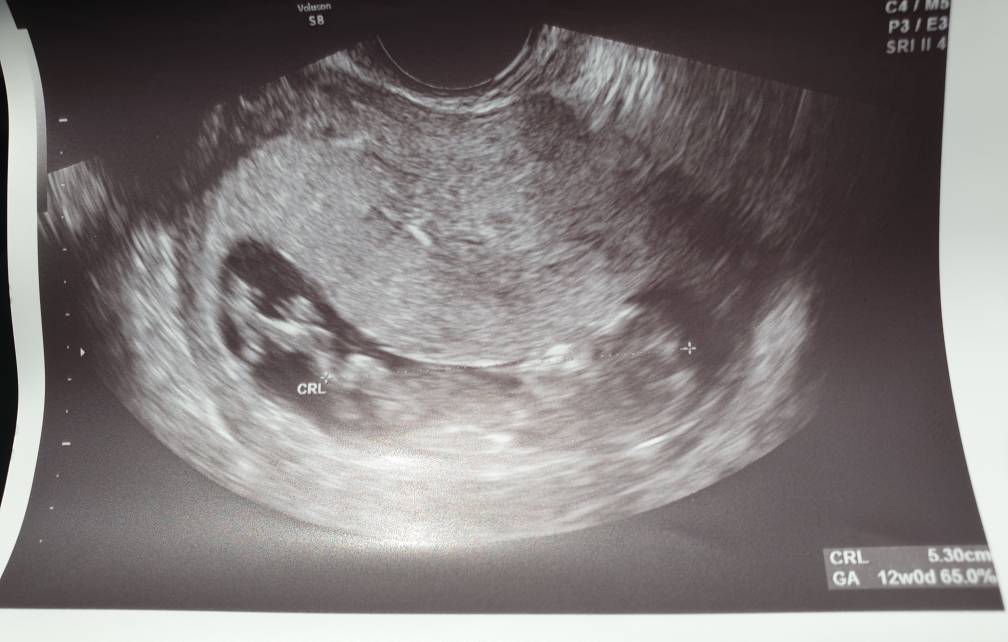

Niestety nie ma opcji by tu cokolwiek odczytać :/

Ja nawet nie widzę zarysu nuba - wybacz.

No nic to zostaje mi czekać ;) następne mam za 2 tygodnie i zjem przed badaniem coś słodkiego to może mały śpioszek będzie lepiej współpracował i pokaże więcej [emoji4]